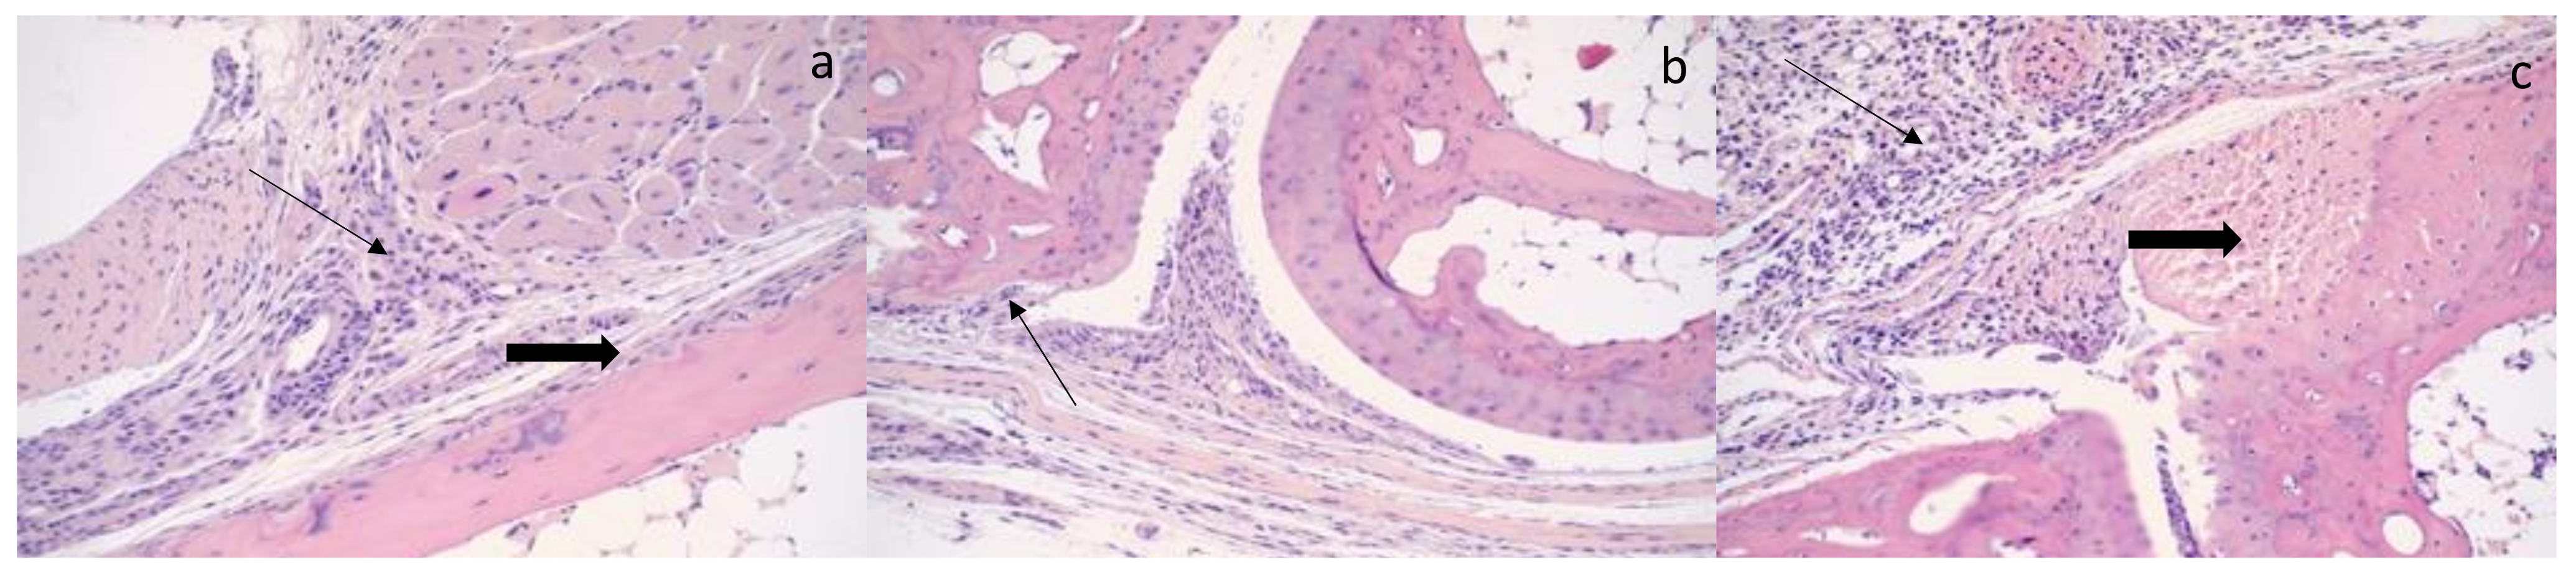

3.4. Histologic Findings: CHIKV SAH2123 Infection Results in Histologic Evidence of Arthritis, Synovitis, Periostitis and Myositis That Persist to 21 DPI